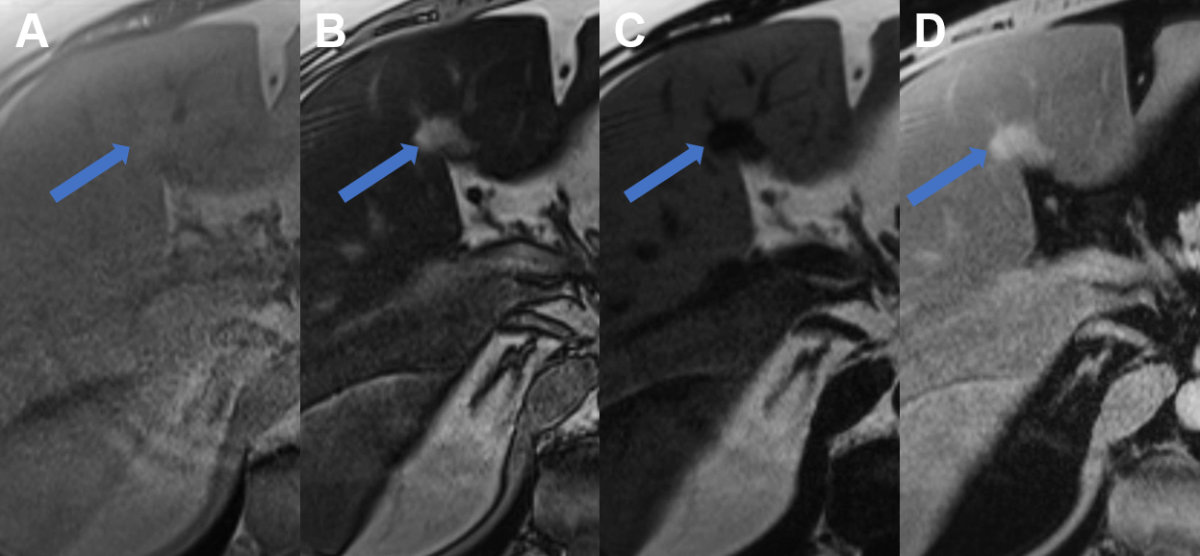

On CT, steatosis will result in decreased (hypodense) attenuation on non-contrast scans, with normal liver attenuation of 50–57 Hounsfield unit (HU) remaining. The attenuation will remain hypodense compared to normal liver and the spleen during the portal venous phase at about 70 seconds. However, MRI should be used as the next non-invasive imaging modality in unclear cases due to its superior ability to detect fat after conventional ultrasound / CEUS (figure 4). MRI can demonstrate microscopic fat content resulting in signal intensity drop from in-phase to opposed-phase imaging. MRI even allows to quantify the fat content [26].

Figure 4Regional fatty sparing and focal steatosis on MRI. A MRI T1 weighted image of a case with focal sparing (arrow) of steatosis in the porta hepatis with B signal drop in the remaining liver on opposed phase images and persisting high signal in the spared area. C On fat only images, the fatty liver shows signal with the spared area appearing dark, while on D the water only image, the spared area is brighter than the steatotic surrounding liver.